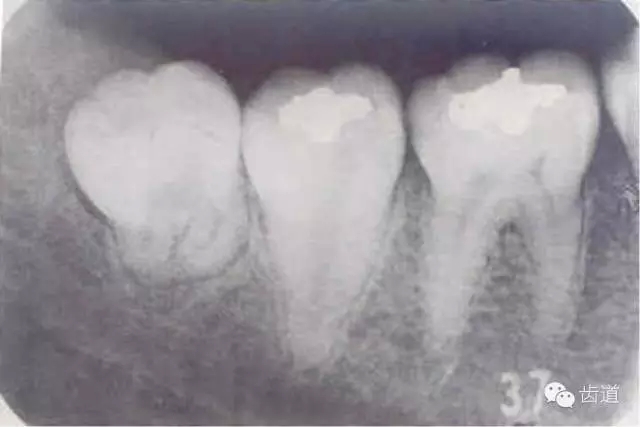

1.智齒萌出不全

2.牙冠周?chē)浗M織紅腫、糜爛、觸痛

3.齦瓣處形成盲袋,內(nèi)有膿性分泌物,有時(shí)形成冠周膿腫

4.嚴(yán)重時(shí)可見(jiàn)咽側(cè)壁及舌腭弓紅腫,患側(cè)頜下淋巴結(jié)腫大、壓痛。